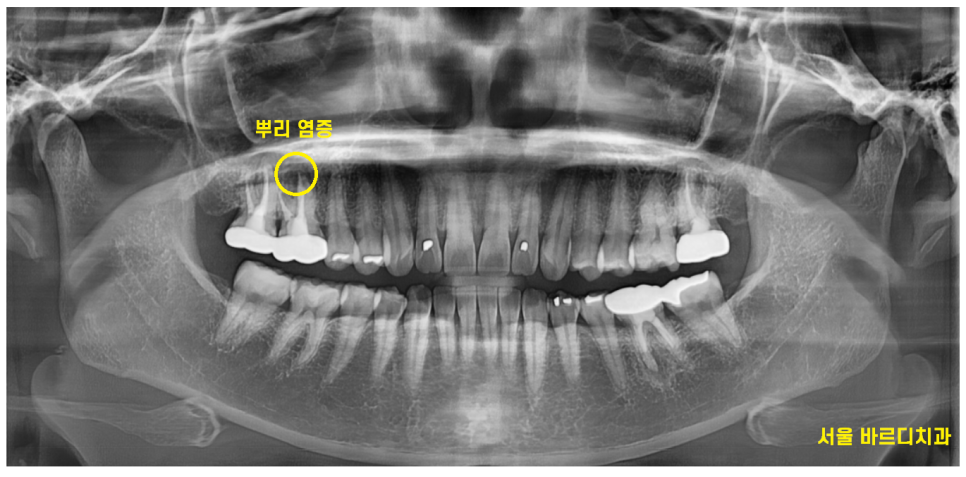

x-ray상에서는 뿌리에 염증이 생긴치아가

눈에 들어왔습니다.